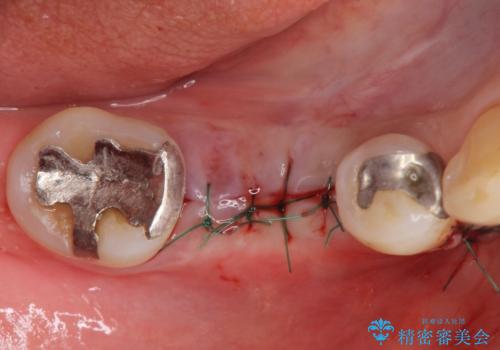

- 歯茎が腫れて痛いとの事で来院。

保存できない状態でしたので抜歯をして歯槽堤保存術を行いました。その後大臼歯部にインプラント治療を行いました。